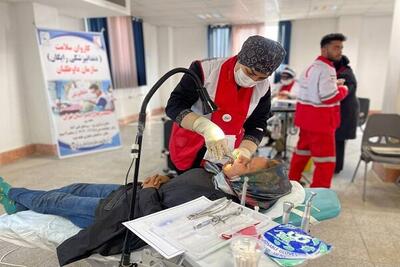

معرفی خدمات اقساطی در کلینیکهای دندانپزشکی تهران

در سال های اخیر افزایش تعرفه دندانپزشکی در کلینیک دندا�